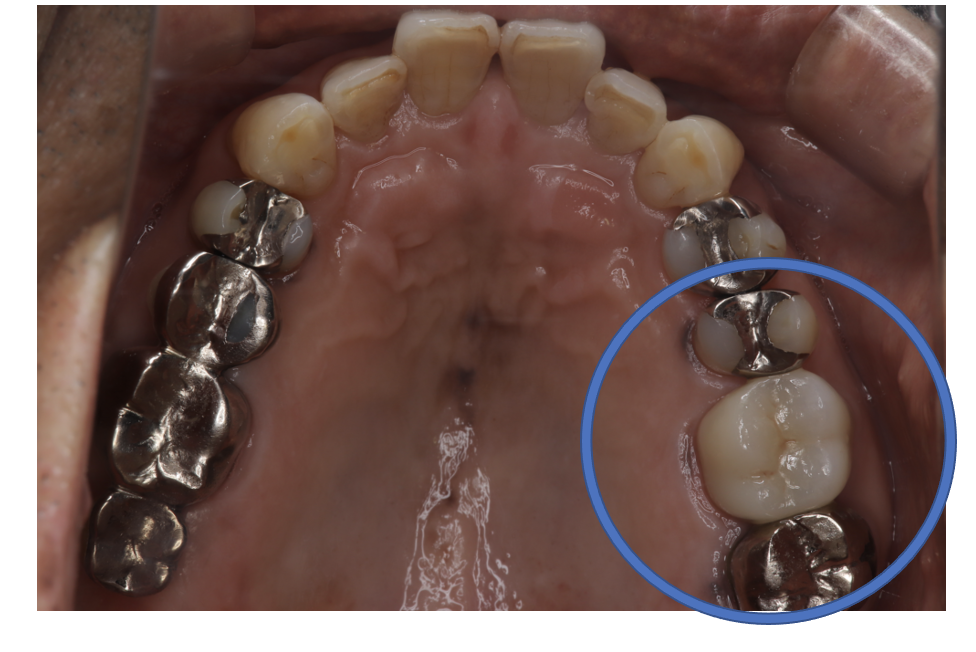

クラウンフルジルコニア

フルジルコニアCr 9 No.31

Before

After

| 治療方法 | フルジルコニアCr 虫歯などで失った歯質を天然歯と同じ色・質感のセラミックの一種であるジルコニア(人工ダイヤモンド)で補う治療法。 |

| 治療のデメリット | 変色がなく耐久性の高い治療ですが、歯周病や二次虫歯を予防するためには歯科医院での定期的なメインテナンスが大切です。 |

| 費用 | ¥89,000 |

| 通院回数 | 1ヶ月〜6ヶ月 |

| 備考 | 院長より 銀歯の内部に虫歯が進行してしまっていたケースです。中を開けて見てみると、外から想像するよりもはるかに虫歯が広がってしまっていました。幸運にも神経を保存できたので、生きた臓器としてまだ使うことが可能です。残存歯質がかなり薄く弱くなってしまったので、ジルコニアで被せて守ってあげています。反対側の歯は、残念ながら虫歯の進行が神経まで及んでいて、根の治療が必要になってしまったケースです。 |